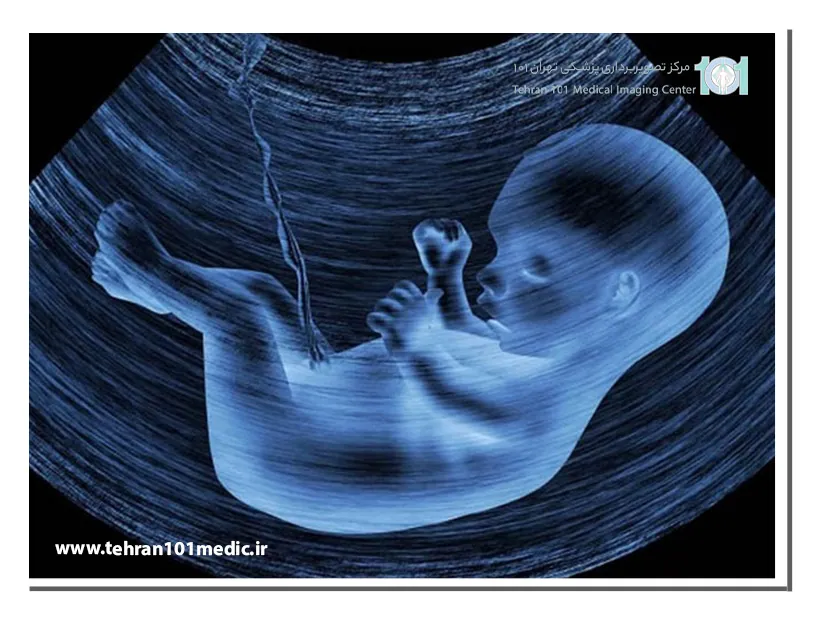

در سونوگرافی آنومالی، متخصص سونوگرافی از یک پروب مخصوص برای ارسال امواج صوتی به داخل رحم استفاده میکند. این امواج صوتی پس از برخورد به اندامهای جنین، بازتاب میشوند و توسط پروب دریافت میشوند. سپس، این امواج صوتی بازتابشده توسط یک کامپیوتر به تصاویر تبدیل میشوند.

در طول این آزمایش، پزشک یا تکنسین سونوگرافی، یک ژل مخصوص روی شکم مادر می مالد. سپس با استفاده از یک دستگاه سونوگرافی که امواج صوتی با فرکانس بالا تولید می کند، تصاویری از جنین بر روی صفحه نمایش ایجاد می شود. این امواج صوتی هیچ آسیبی به مادر یا جنین وارد نمی کنند و تنها به عنوان یک ابزار تصویربرداری استفاده می شوند.

در طول سونوگرافی آنومالی، پزشک به دقت اندازه، شکل و موقعیت اندام های مختلف جنین را بررسی می کند. این شامل اندازه گیری دور سر، دور شکم، طول استخوان ران و بررسی قلب، مغز، ستون فقرات، کلیه ها، مثانه و اندام های گوارشی می شود. همچنین، پزشک به دنبال هرگونه ناهنجاری یا مشکلی در ساختار بدن جنین می گردد.